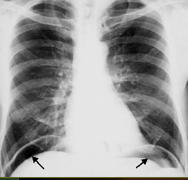

What does this show?

sickle-shaped free air on both sides under the diaphragm

What do you see?

free air of large quantity

supine view

white arrows: crescents of air seen beneath each hemidiaphragm

blue arrows: both sides of the bowel wall are visible